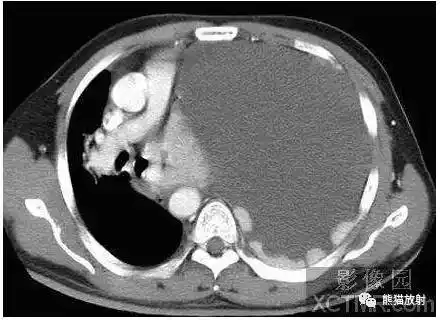

详解胸腔积液形成机理及各类影像表现